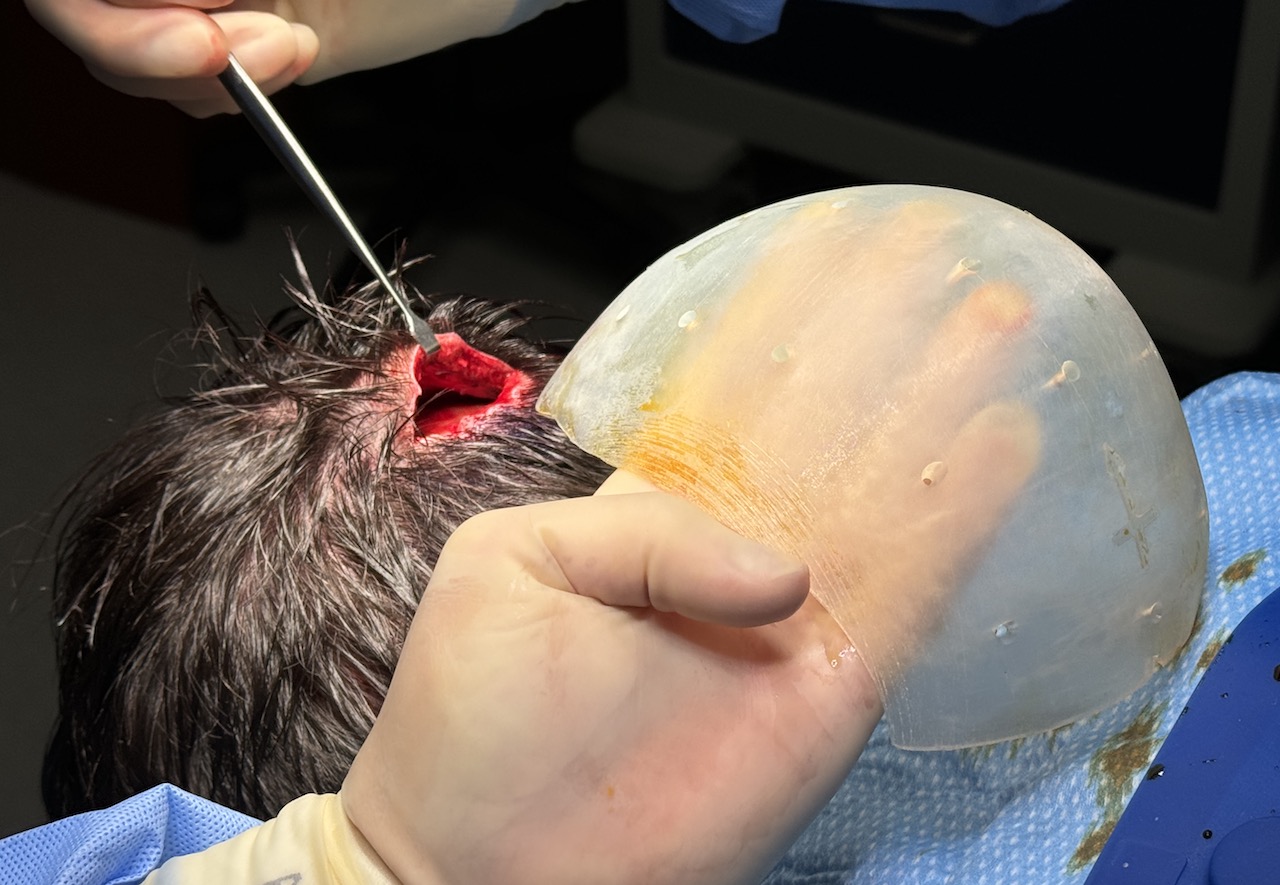

Desire for reduction of prominent occipital knob deformity.

Intraoperative result from occipital knob skull reduction through a direct small scalp incision.

Desire for reduction of prominent occipital knob deformity.

Intraoperative result from occipital knob skull reduction through a direct small scalp incision.